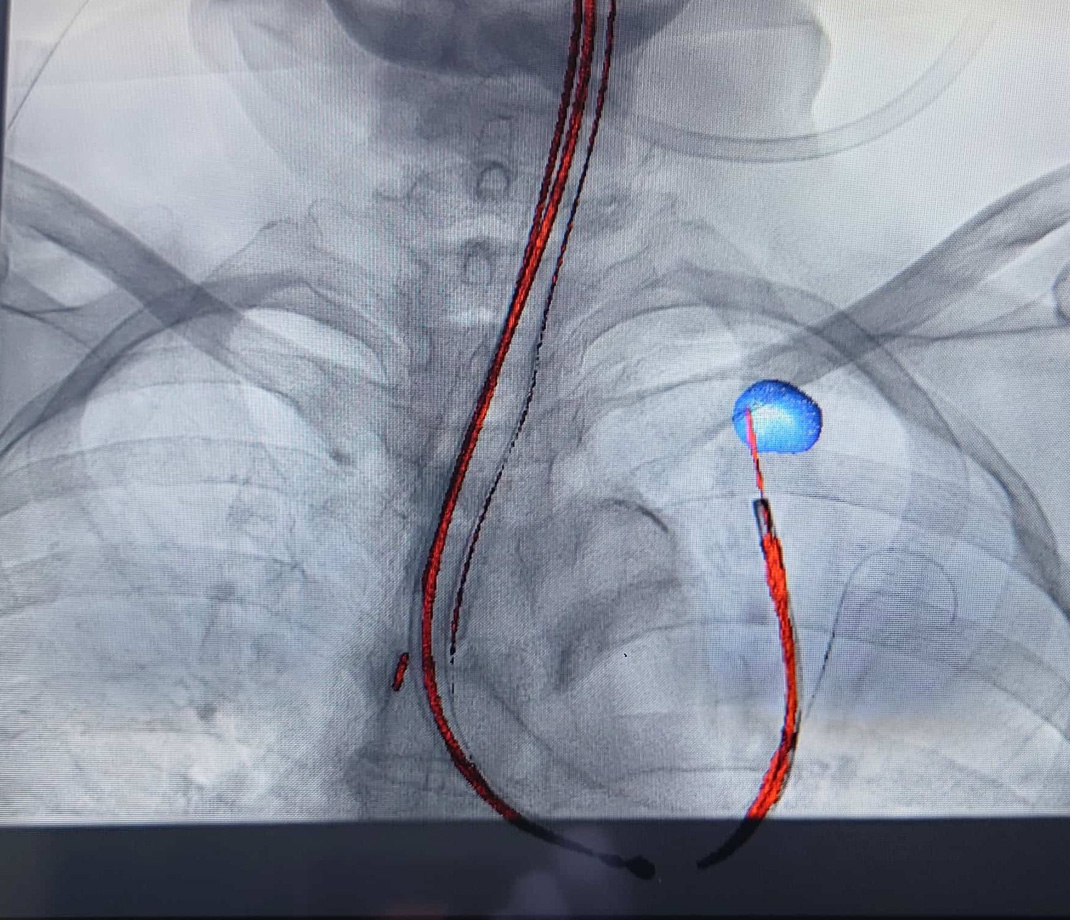

図2 仮想気管支鏡ナビゲーション:検査前に設定した病変(青い丸)への気管支ルート(青い線)が青線で表示されるので、これに従い気管支鏡を挿入します。

図3 コ-ンビームCTによる拡張X線透視:気管支鏡検査中にコーンビームCTを行い、到達確認やX線透視上に病変(青色で表示)を描出することができます。